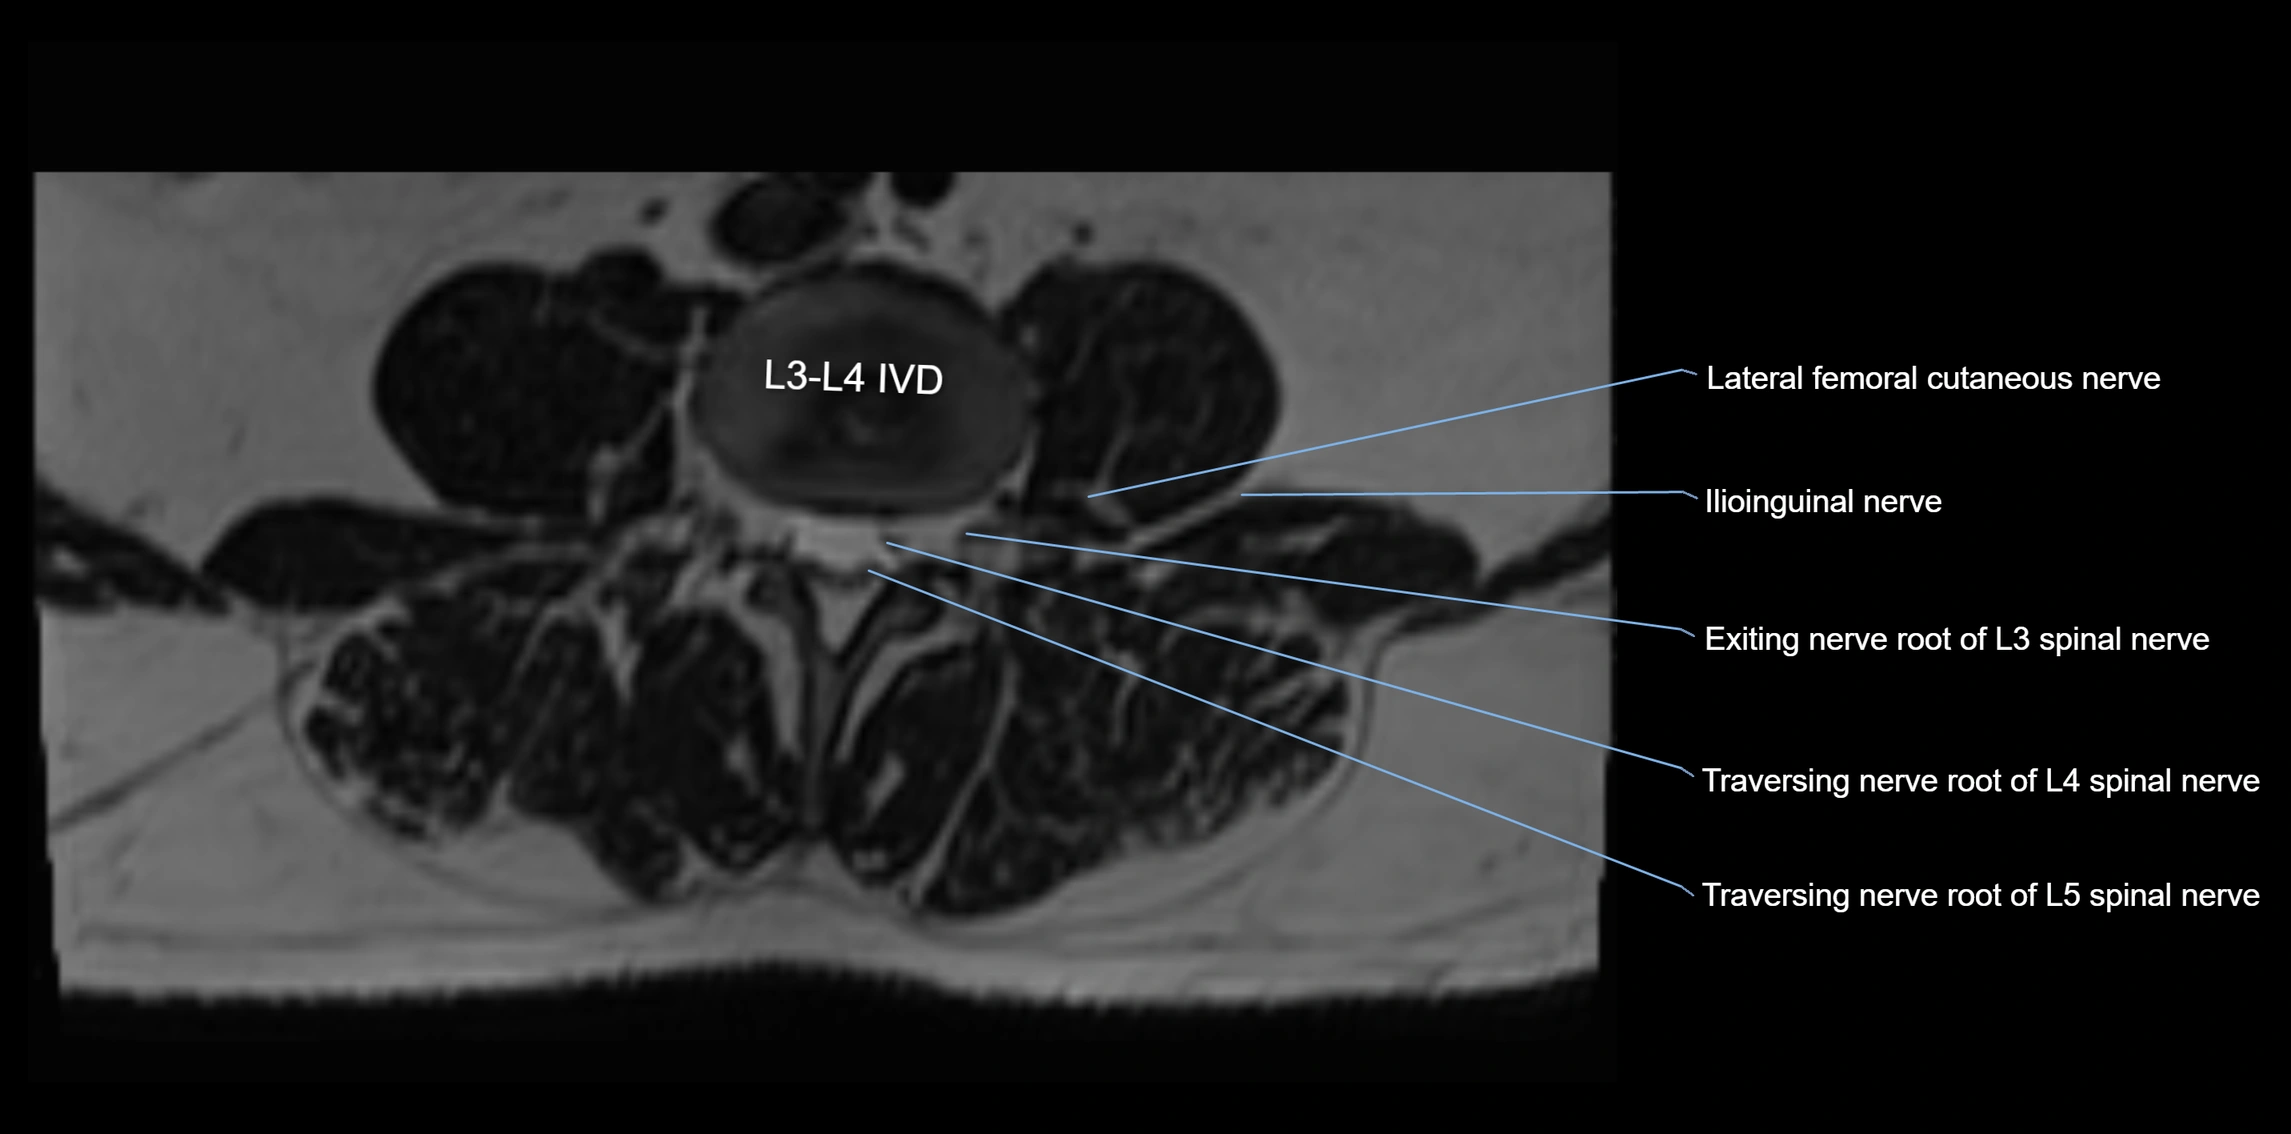

MRI image

image